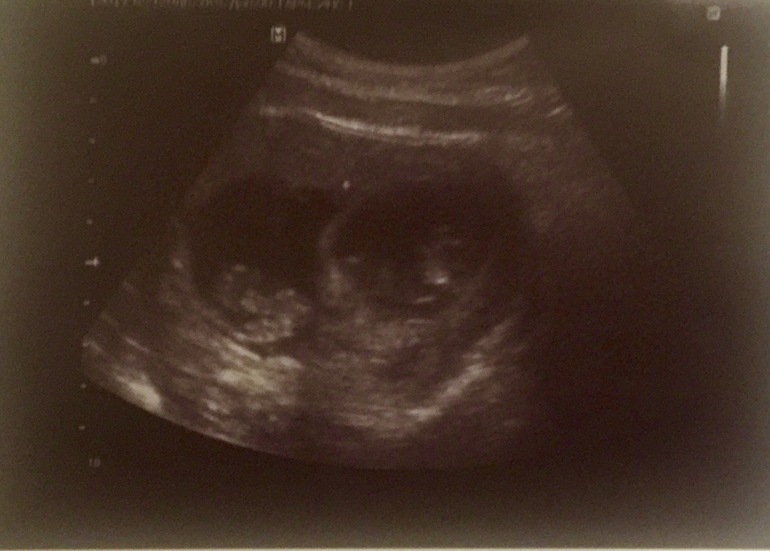

Тоже видно что одно ПЯ меньше. Срок только побольше на снимке - 10я неделя.

Спасибо!Да чем то похоже, но у меня один как бы прячется за другого)буду надеяться что к 12 неделям хоть немного сравняются)Легкой беременности Вам,и удачи))